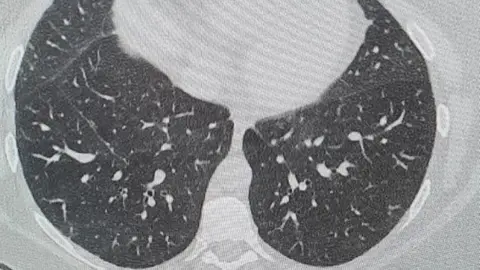

Just as we came home and were trying to get our life on track, they confirmed I had lung disease and it's never going to get any better.

With the lung disease, I have to have lung function tests and I am due to have breathing tests. I will be constantly on medication and I also have a thyroid problem since having Covid.